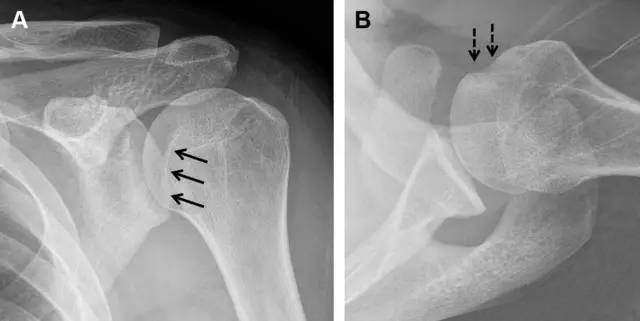

图7 肩关节后脱位伴有反 Hill–Sachs 损伤。(A)外旋位前后位片可见一硬化带(黑箭头),此「凹槽征」与肱骨头关节面平行;(B)腋位片进一步证实了骨折的存在